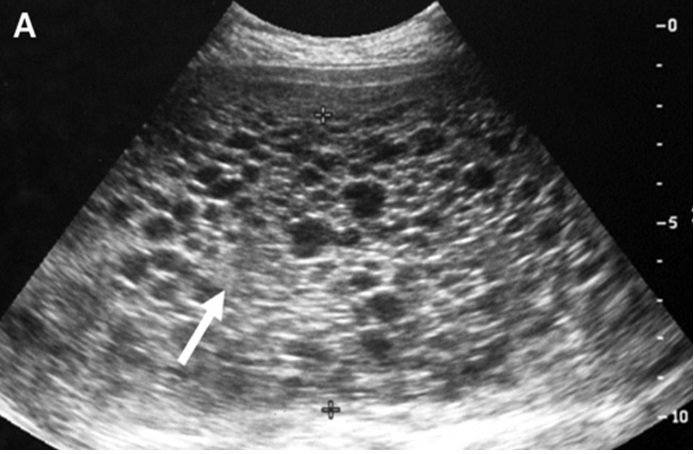

- Siêu âm: Siêu âm là phương pháp chẩn đoán chính xác nhất để xác định thai trứng toàn phần. Bằng cách sử dụng sóng siêu âm, bác sĩ có thể xem xét kích thước và hình dạng của thai trứng để xác định liệu nó có phát triển đúng cách hay không.